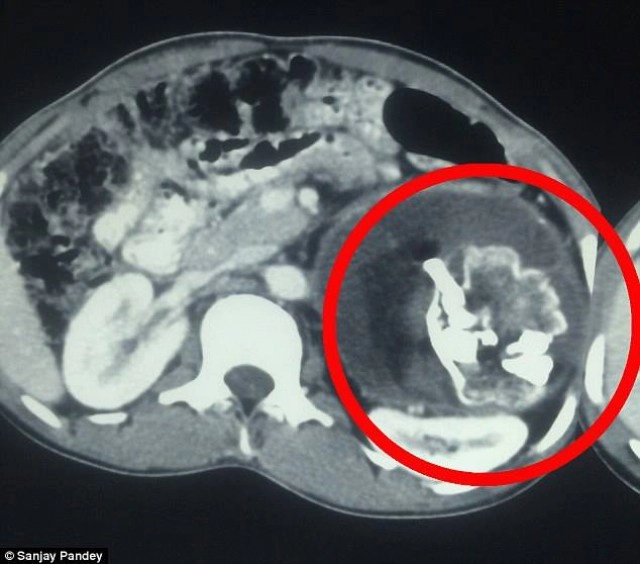

เว็บไซต์เดลิเมล์ ได้เปิดเผยเรื่องราวน่าขนลุกเมื่อเด็กหนุ่มวัย 18 ปี จากรัฐอุตตรประเทศของอินเดีย ตรวจพบแฝดปรสิตอยู่ในท้อง โดยมีลักษณะเป็นกะโหลกที่เจริญผิดรูปร่างหนัก 2.5 กิโลกรัม ยาว 20 เซนติเมตร มีกระดูกสันหลัง ฟัน และผมยาวถึง 2 เมตร

ด้านแพทย์ได้ทำการสแกนและเอ็กซ์เรย์ช่องท้อง พบว่ามีก้อนกระดูกประหลาดอยู่ในท้อง หรือที่เรียกว่า แฝดปรสิต (Foetus in fetu) เป็นภาวะความผิดปกติด้านพัฒนาการของตัวอ่อนแฝดระหว่างอยู่ในครรภ์ ทั่วโลกตอนนี้พบเพียง 200 กรณี และที่อินเดียเกิดขึ้น 2 ครั้ง

แฝดปรสิต (Foetus in fetu) ฝังตัวอยู่ในร่างกายของนเรนทรามาตั้งแต่เกิด เป็นสาเหตุทำให้เขามีอาการป่วยโดยช่วงแรกแพทย์ไม่สามารถวินิจฉัยได้ จนกระทั่งเมื่อวันจันทร์ที่ผ่านมา ซึ่งแพทย์ใช้เวลากว่า 3 ชั่วโมงในการผ่าตัดนำแฝดปรสิตออกมา โดยมีลักษณะเป็นกระโหลกที่เจริญผิดรูปร่างหนัก 2.5 กิโลกรัม ยาว 20 เซนติเมตร มีกระดูกสันหลัง ฟัน และเส้นผมซึ่งยาวถึง 2 เมตร